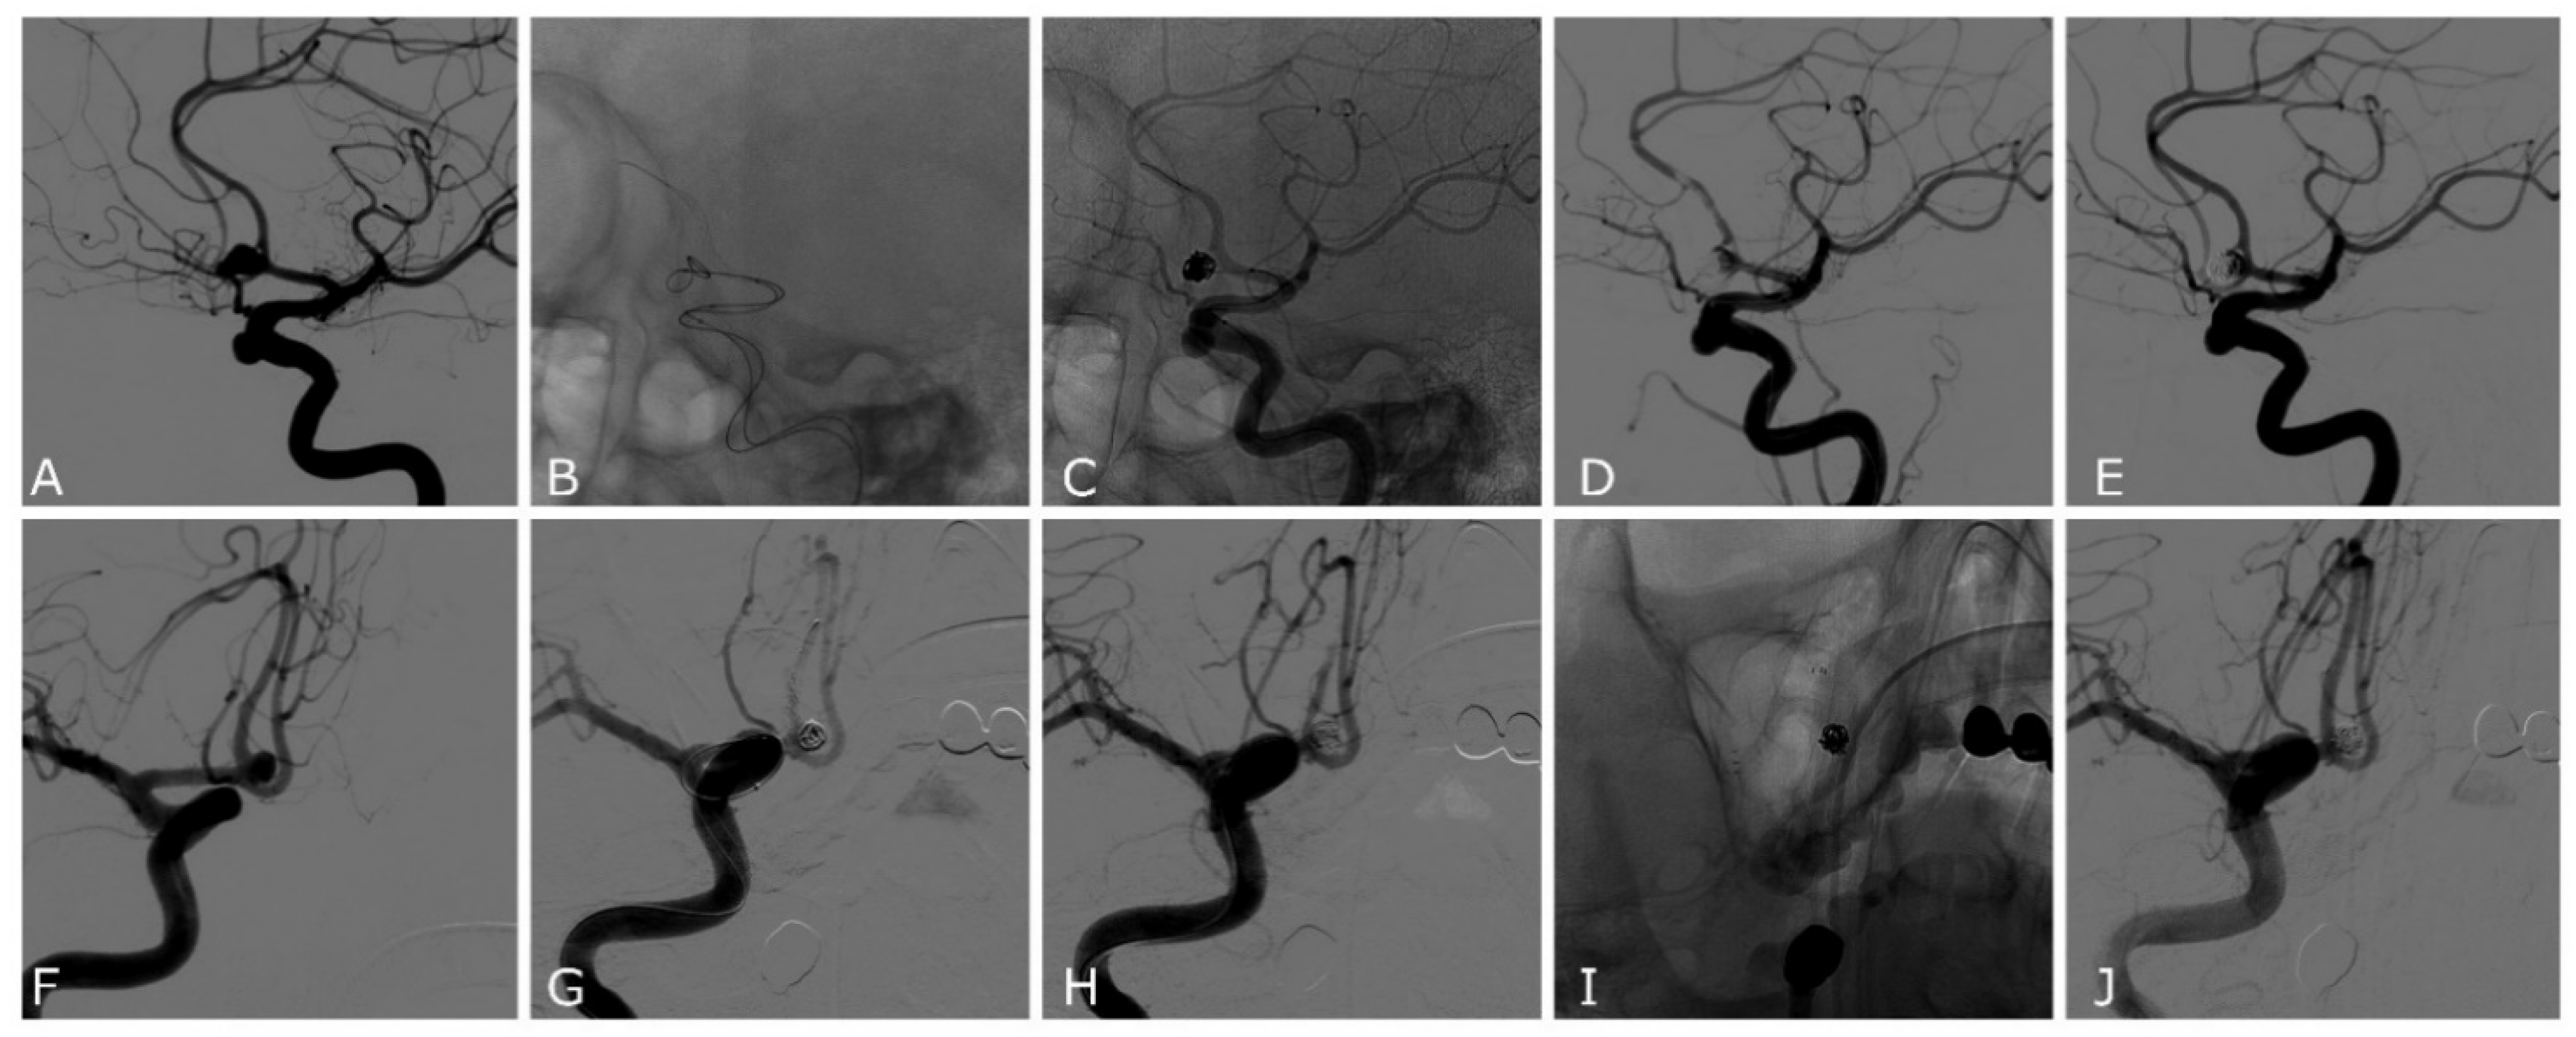

| Case | Age | Sex | Location | SAH | Max Size (Height, Width, Neck) mm | Device | Complications | Rescue Treatment | mRR | mRs at 3 Months |

|---|---|---|---|---|---|---|---|---|---|---|

| 1 | 74 | F | PCOM | No | 4.2, 7, 4 | Comaneci | - | I | 0 | |

| 2 | 65 | M | PCOM | Yes | 3.1, 4, 3 | 17 | - | I | 0 | |

| 3 | 70 | F | PICA | Yes | 3.5, 2, 1.5 | Comaneci | - | I | 0 | |

| 4 | 86 | F | PCOM | Yes | 6.4, 4.3, 5.5 | Comaneci | Intra-Comaneci and parent artery clot formation | Stent | II | 6 |

| 5 | 59 | F | ACOM | Yes | 10, 6.2, 5.5 | 17 | - | II | 0 | |

| 6 | 65 | F | PCOM | No | 6.7, 3.9, 3 | Petit | - | II | 0 | |

| 7 | 51 | F | MCA | No | 2, 2.2, 2 | Petit | - | II | 5 | |

| 8 | 65 | M | ACOM | Yes | 5.7, 3.7, 3.5 | 17 | - | 0 | ||

| 9 | 77 | F | PCOM | Yes | 8, 10.3, 5.9 | Comaneci | Intra-Comaneci clot formation | I | 0 | |

| 10 | 65 | F | ACOM | Yes | 3, 2.4, 2 | 17 | - | I | 5 | |

| 11 | 45 | M | ACOM | Yes | 5.5, 3.6, 2.8 | 17 | Intra-Comaneci clot formation | IIIb | 1 | |

| 12 | 62 | F | ACOM | Yes | 9, 4.5, 3 | 17 | Intra-Comaneci clot formation | Stent | IIIb | 0 |

| 13 | 55 | M | ACOM | Yes | 14.5, 15.6, 8.2 | 17 | - | I | 0 | |

| 14 | 61 | M | ACOM | Yes | 3, 5.9, 5 | 17 | Intra-Comaneci clot formation | II | 0 |